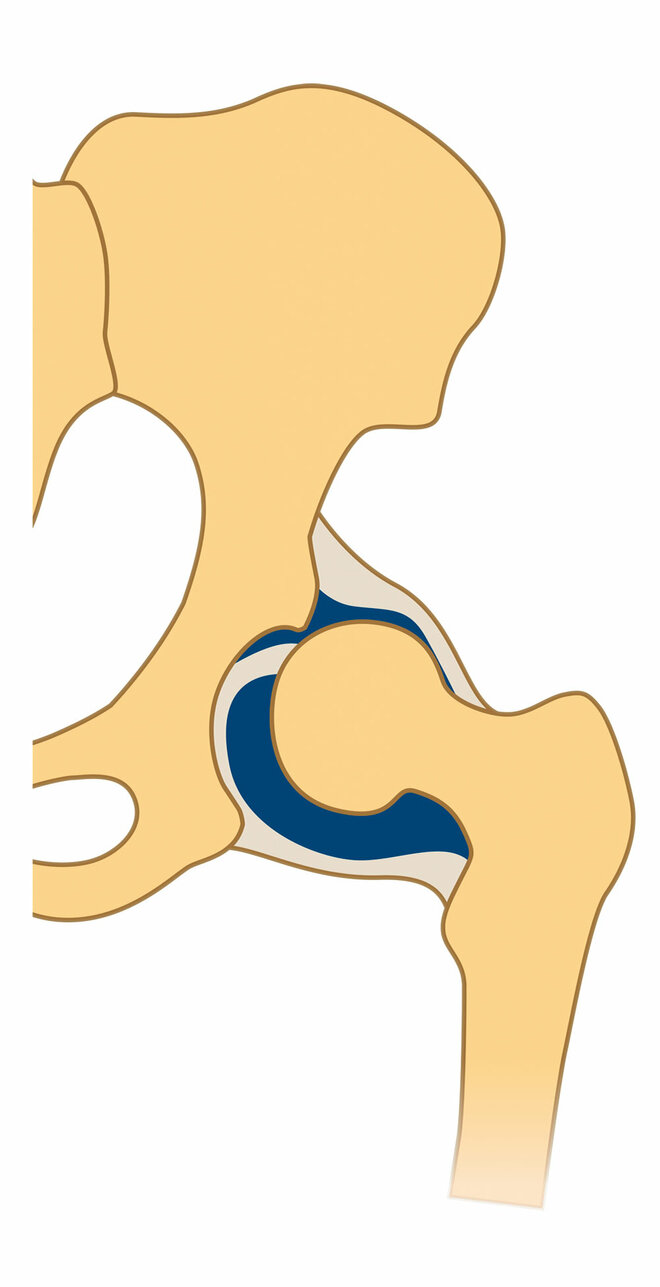

In den meisten Fällen löst sich das Problem in den ersten Lebenswochen von alleine. Bei etwa einem Prozent aber, sagt Ziegler, bleibe eine mehr oder weniger ausgeprägte Fehlstellung und Störung der Knochenreifung bestehen. Und bei maximal einem weiteren Prozent sei sie so stark, dass der Hüftkopf aus der Pfanne zu springen droht oder bereits gesprungen ist (siehe Infografik unten).

Drei Formen der Hüftreifestörung

Bei Kindern mit drohender Luxation, also wenn der Hüftkopf in der Pfanne gehalten werden muss, sowie bei leichter ausgeprägten Dysplasien reichen in der Regel Spreizhosen. "Sie halten über Schienen beide Hüftgelenke gebeugt und gespreizt, wodurch die Hüfte den Reiz bekommt, nachzureifen", erklärt Kinderärztin Brunnert.